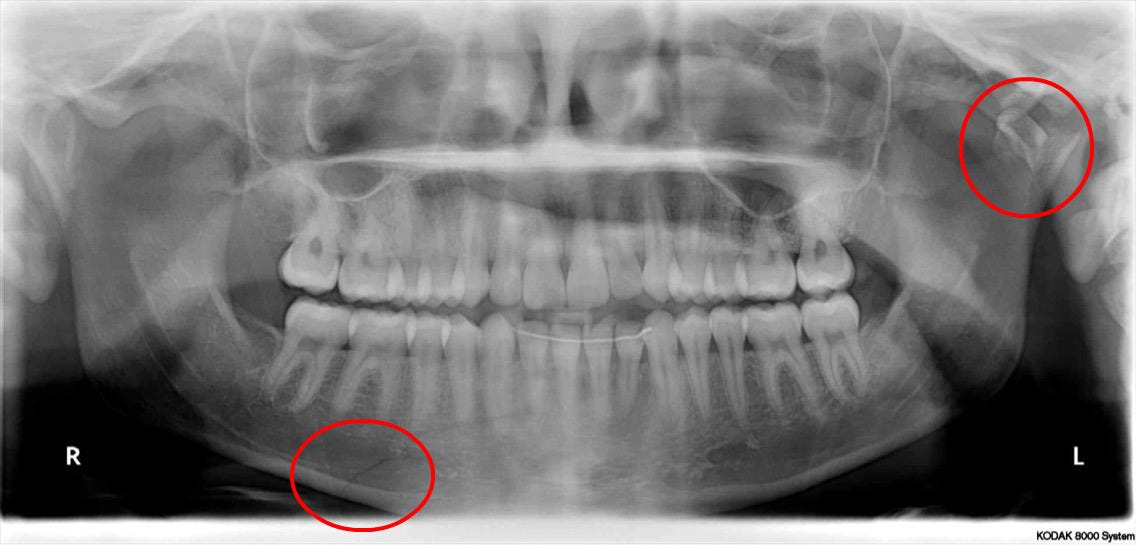

Dislocated Jaw X Ray Collection 2022 Dislocated Jaw X Ray Collection 2022

Dislocated Jaw X Ray

Learning Radiology - Dislocated, Mandible, Mandibular, Dislocation Dislocated Jaw: Symptoms and Treatment Bilateral temporomandibular joint dislocation | Radiology Case ... Pretreatment X-ray showing the anterior dislocation. | Download ... Learning Radiology - Dislocated, Mandible, Mandibular, Dislocation Dislocated Jaw X Ray